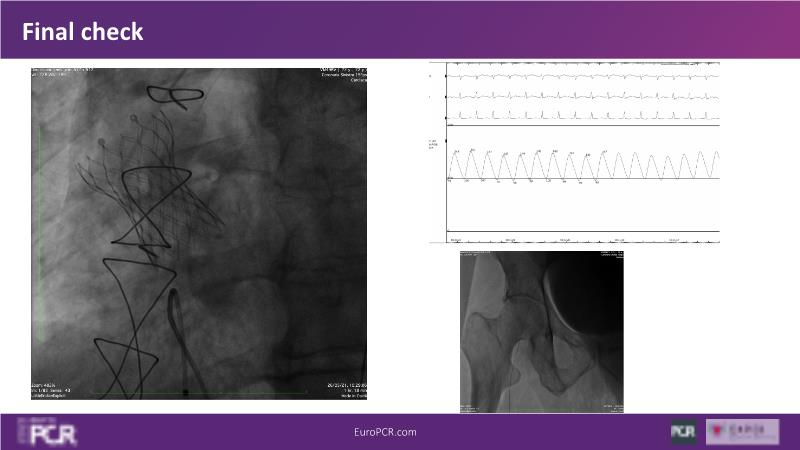

Discover the key factors to consider in selecting the optimal valve and implant technique for transcatheter aortic valve implantation (TAVI) to achieve optimal procedural outcomes. Gain insights into the impact of device choice and implantation technique on coronary access following TAVI and learn valuable strategies for tailoring your TAVI technique to complex scenarios, including bicuspid aortic valves, large and calcified anatomies, and ensuring coronary access.

- To learn what to consider when determining valve selection for TAVI

- To appreciate the impact of device choice and implantation technique on coronary access after TAVI

- To learn how to tailor your TAVI technique to complex situations: bicuspid aortic valves, large, calcified anatomies and coronary access